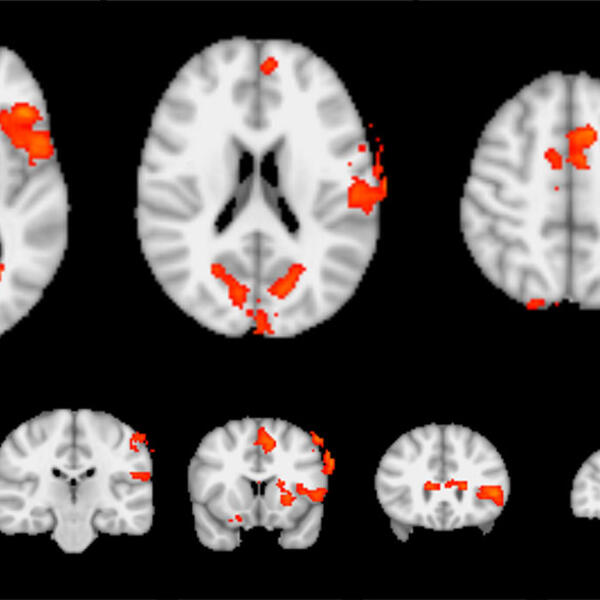

Novel Treatment for Chronic Tinnitus